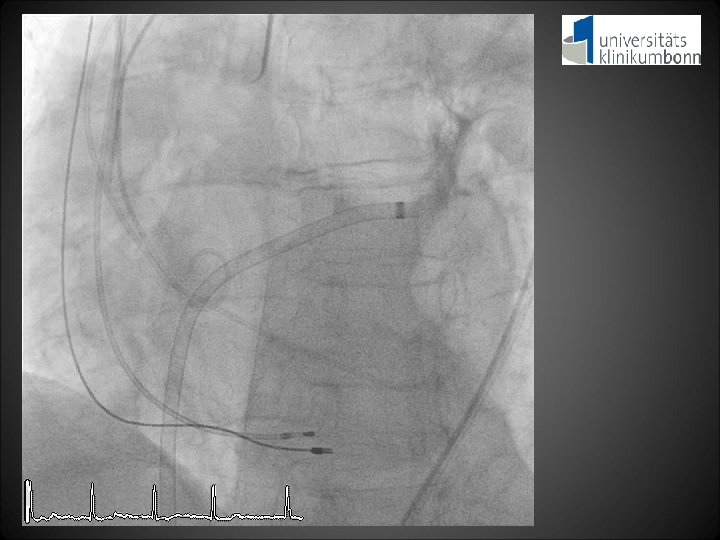

Clinical course post-TAVI • Patient stable without need for catecholamines after the procedure • Development of acute kidney injury on day 2 • Acute cardiorenal syndrome with pleural effusions and dyspnea NYHA IV

RRsys 120 mm. Hg RRdia 40 mm. Hg LVEDP 20 mm. Hg Aortic regurgitation Index = [(RRdia – LVEDP) / RRsys] x 100 = [(40 – 20) / 120] x 100 = 16. 7

13. 20 mm +1. 5 mm 12. 33 mm +1. 5 mm

4. 18 mm -9. 0 mm 3. 16 mm -9. 2 mm